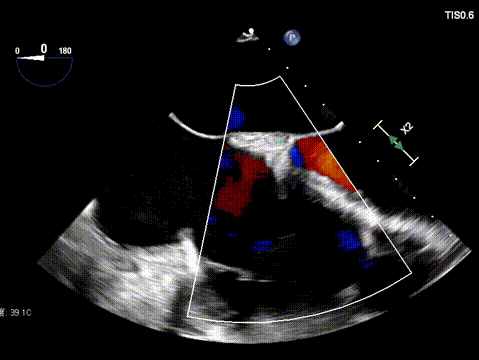

1. Regurgitation Effect: Reduced from massive (5+) to moderate (2+).

Postoperative

Ultimately, the tricuspid annulus was significantly reduced, and regurgitation was downgraded from critical to mild‑to‑moderate.